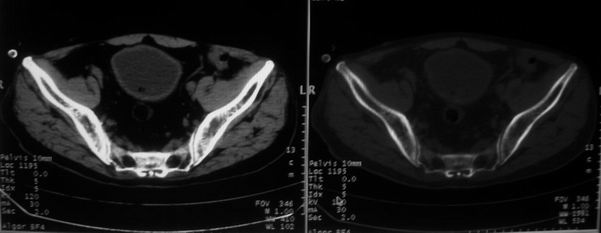

男,85岁,排尿困难。骶椎有问题吗?

前列腺明显增大,突入膀胱,各叶比例协调,密度均匀,精囊腺及精囊角正常;考虑良性增大。

骶骨没有看到明显异常。

1)前列腺明显增大,突入膀胱,各叶比例协调,密度均匀,精囊腺及精囊角正常;考虑前列腺增生症并阻塞性膀胱炎。2)骶椎右侧类似囊状骨质密度减低区,边缘骨质硬化,其内为软组织密度影填塞,相邻之骶椎椎管受压变形;考虑为骶椎右侧囊肿或神经纤维瘤。

建议:行mri检查。